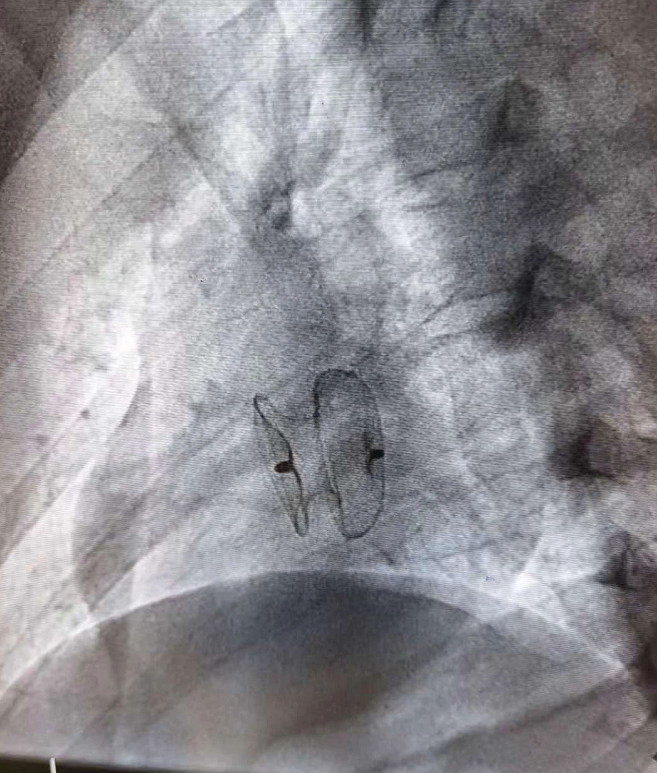

房间隔缺损封堵器

房缺封堵器影响表现